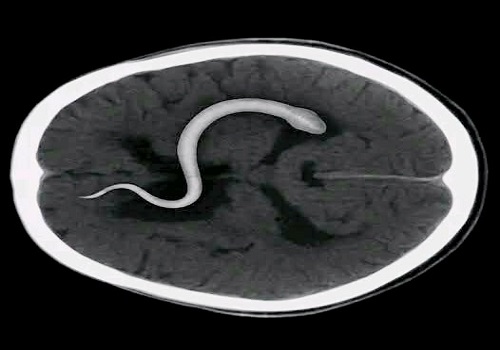

لكن بعد أن سقط الرجل في الحمّام نتيجة نوبة دوارٍ حادة، أجرى فحوصاتٍ دقيقة وأشعة رنين مغناطيسي، فكانت الصدمة: دودة شريطية حيّة تعيش داخل دماغه منذ أكثر من عشر سنوات، وتتغذّى ببطءٍ على أنسجته العصبية!

وفي عمليةٍ طارئة، تمكّن الأطباء من استخراج الدودة بطول نحو سبعة سنتيمترات، وكانت لا تزال حيّة.